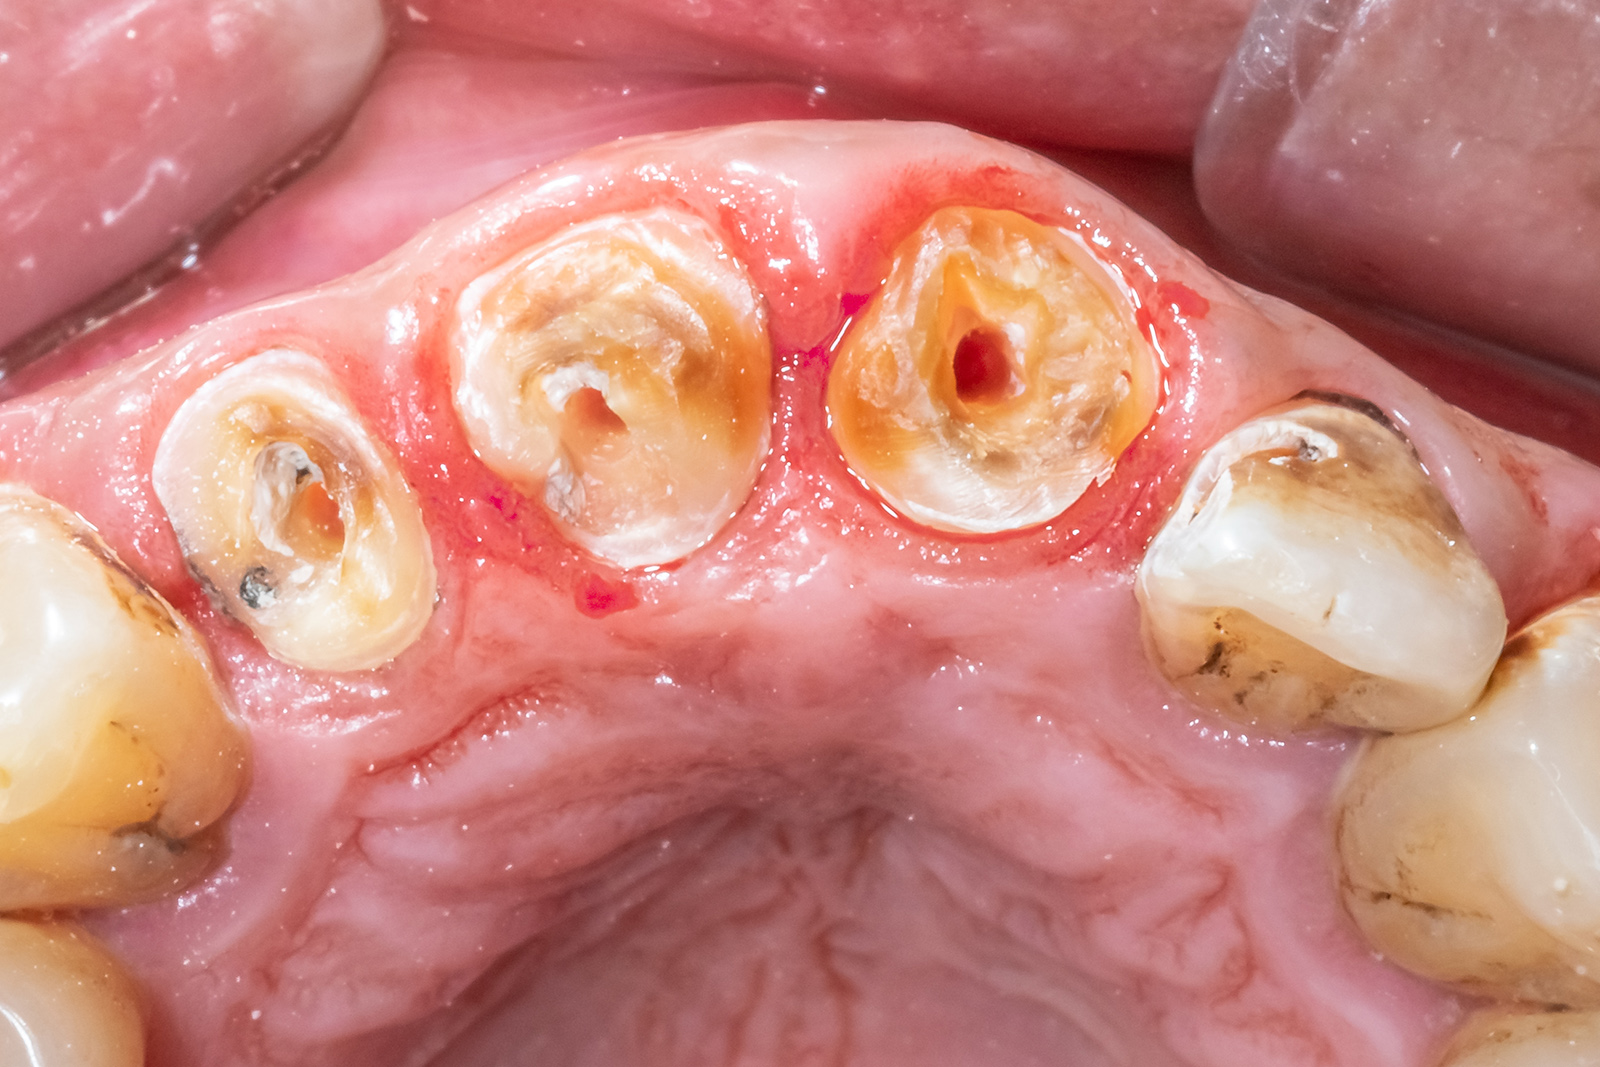

「削りすぎない」虫歯治療

かつての虫歯治療は、詰め物が外れないように虫歯の周囲まで大きく削り、全体を覆うような治療が主流でした。

しかし、健康な部分まで削りすぎてしまうと、再治療が必要になった際に削る場所が残っておらず、最悪の場合は「抜歯」を宣告されることになりかねません。

歯の寿命を延ばすためには、悪いところだけを丁寧に取り除き、健康な部分はできるだけ多く残すことが何よりも大切です。

「マイクロスコープ」と「高倍率ルーペ」による精密治療

虫歯と健康な歯の境目を肉眼だけで完璧に見分けることには、どうしても物理的な限界があります。

そのため当院では、すべての処置において「マイクロスコープ」や「高倍率ルーペ」を駆使し、拡大視野での治療に臨んでいます。

患部を十数倍もの大きさで鮮明に捉えることで、虫歯だけ」を徹底的に取り除く、高精度な治療を可能にしています。